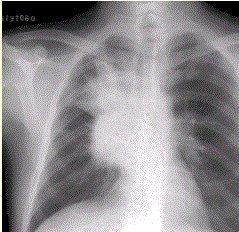

问题 患者男,62岁,痰中带血丝2周,无发热,伴刺激性咳嗽。X线胸片如下图。应诊断为

选项 A.右上肺结核并肺门淋巴结增大 B.肺动脉高压 C.右肺中心型肺癌 D.右肺脓肿 E.升主动脉瘤

答案 C